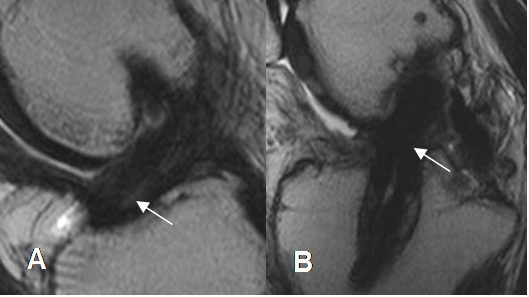

Fig 141. Ruptura del injerto.

A: RM sagital en T1 y B: RM sagital en STIR. Solución de continuidad del injerto, por ruptura completa.

Fig 142. Ruptura del injerto.

A: RM sagital en T2. Pérdida de la tensión y orientación en las fibras del injerto, sospechando su ruptura.

B: ArtroRM sagital en STIR. Se confirma la ruptura de injerto, con interrupción de sus fibras.